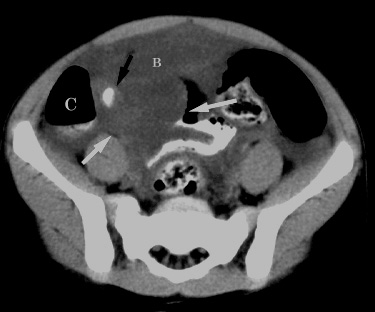

| Non-perforated appendicitis with multiple

appendicoliths, clinical symptoms mimicking psoas muscle

inflammation. 13 year old boy presented with three day history of right lower quadrant pain after weight-lifting which included squats. There was no history of nausea, vomiting, fever, or leukocytosis. On physical examination, positive peritoneal signs (abdominal guarding and rebound tenderness) were elicited. CT examination was performed to evaluate for possible abscess, shown below. |

Figure 2. CT image just caudal to Figure 1 shows the calcified appendicolith (arrow) obstructing the appendiceal neck. Note multiple dilated ileal loops (I). |

Figure 3. CT image at a lower level than Figure 2 shows a second appendicolith (large white arrow)within the fluid-filled dilated appendix. Note the similarity in appearance to the contrast-filled, dilated right distal ureter (small black arrow on the right; small black arrow on the left is the non-dilated distal left ureter). |